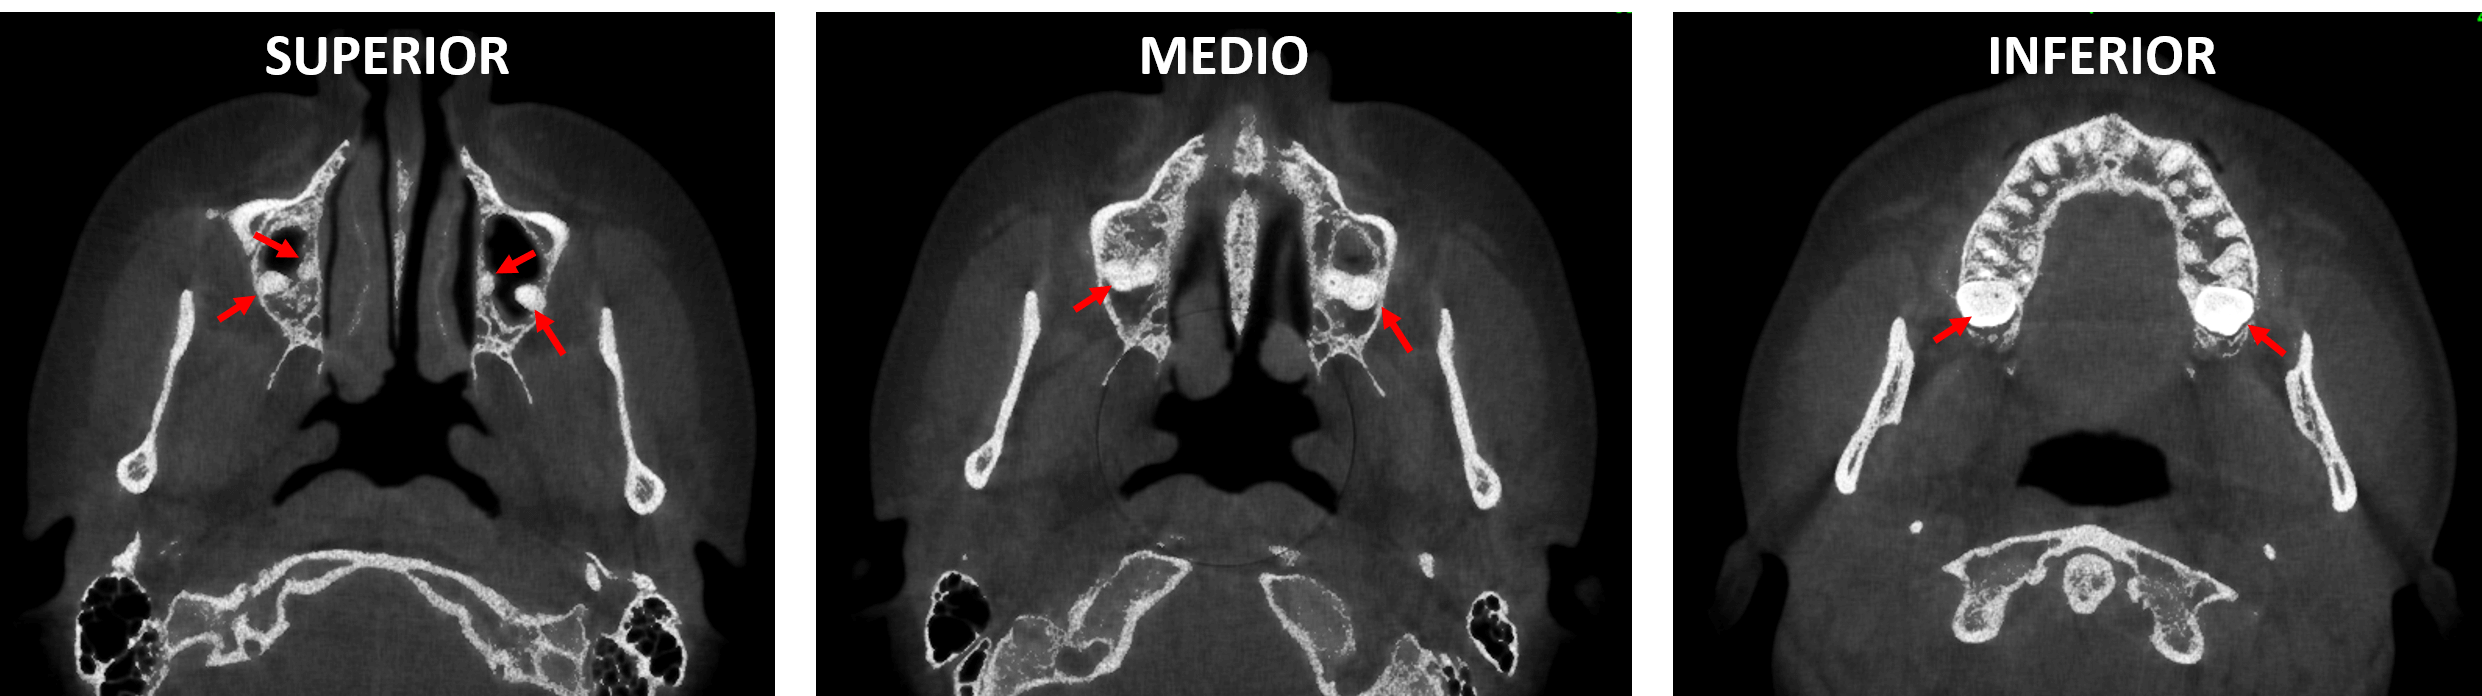

En cortes sagitales (Fig.3) se observa la estrecha relación de los terceros molares de los órganos dentarios 17 y 27, respectivamente, condicionando la impactación vertical de los terceros molares.